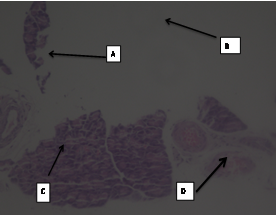

The photomicrographs of normal control group rats showed normal acini, and normal cellular population in the islets of Langerhans in pancreas as shown in (slide 1). Massive cell damage, extensive destruction of cell lining, inflammatory cells, and β-cell damage were seen in diabetic control group (slide 2). There was enlargement of β-cells, increase in vascular spaces with hyperplasia in standard group, i. e. Glibenclamide (slide 3).

The histopathological results of pancreas with FDLEE 100 mg/kg showed exocrine and endocrine tissue at most places intact with few areas showing presence of fatty tissue. The slight damage to the cell lining, slight damage to vasculature and haemorrhages with necrosis were also seen.

The microscopic changes showed significant improvement in the development of islet of Langerhans (slide 4). The microscopic changes in pancreas with FDLEE 200 mg/kg showed haemorrhage with necrosis, damage to the vasculature, normal cell population, slight β-cell enlargement.(slide 5) In the test group FDLEE 400 mg/kg there was increase in vascular spaces, rarely seen mild necrosis and significant β-cell recovery after administration of the extract. (Slide 6).

Fig 4: Slides of pancreas of different treated groups: (1- Normal Control; 2-Diabetic control; 3-Standard; 4-Test I; 5-Test II; 6-Test III) A- Massive cell damage; B- extensive destruction of cell lining; C- inflammatory cells; D- β-cell damage